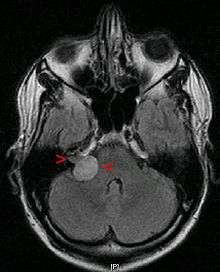

| Bilateral schwannomas in a patient with neurofibromatosis 2 | |

Although there is an inheritable condition called Neurofibromatosis Type 2 (NF2) which can lead to acoustic neuroma formation in some people, most acoustic neuromas occur spontaneously without any evidence of family history (95%).[3] NF2 occurs with a frequency of 1 in 30,000 to 1 in 50,000 births. The hallmark of this disorder is bilateral acoustic neuromas (an acoustic neuroma on both sides) usually developing in late childhood or early adulthood, frequently associated with other brain and spinal chord tumors.